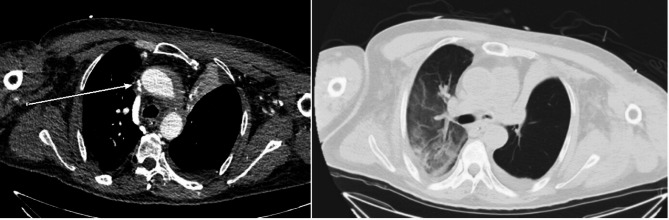

Case presentation: We report the first case of SVC syndrome in an adult patient with pre-existing SVC angulation, exacerbated by cannula placement during VV ECMO therapy. Serial venous-phase chest CT scans (pre-ECMO and during ECMO support) demonstrated progressive luminal narrowing at the cannula tip site, correlating with clinical manifestations of SVC obstruction. The patient was successfully weaned from VV ECMO, achieved complete resolution of SVC syndrome symptoms, and was discharged without neurological sequelae.

Conclusions: This case provides definitive imaging evidence that ECMO cannula placement alone can induce acute SVC stenosis in patients with pre-existing vascular tortuosity. Our findings strongly advocate for pre-procedural vascular imaging assessment and real-time monitoring during ECMO support to mitigate this life-threatening complication.